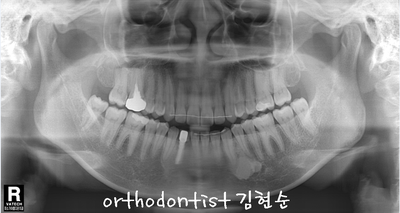

- Treatment plan -

-

치아 사이 공간 해결, 상실 공간 보철 위한 비발치 교정

#42 치아 공간을 벌리고 보철해야 좌우 대칭과 교합이 맞음

상하 교정 장치 부착 → #42 open → 교정 마무리 시기에 implant

예상 교정 기간 약 7 ~ 9 개월

( 김현순 대표 원장님 )

- 화살표 좌/우 방향 공간 확보 후 inplant